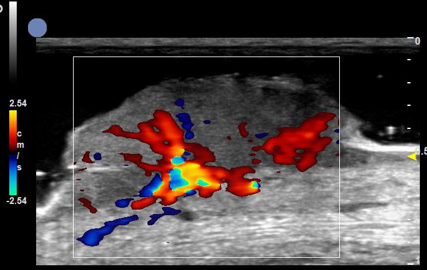

增殖期血管瘤